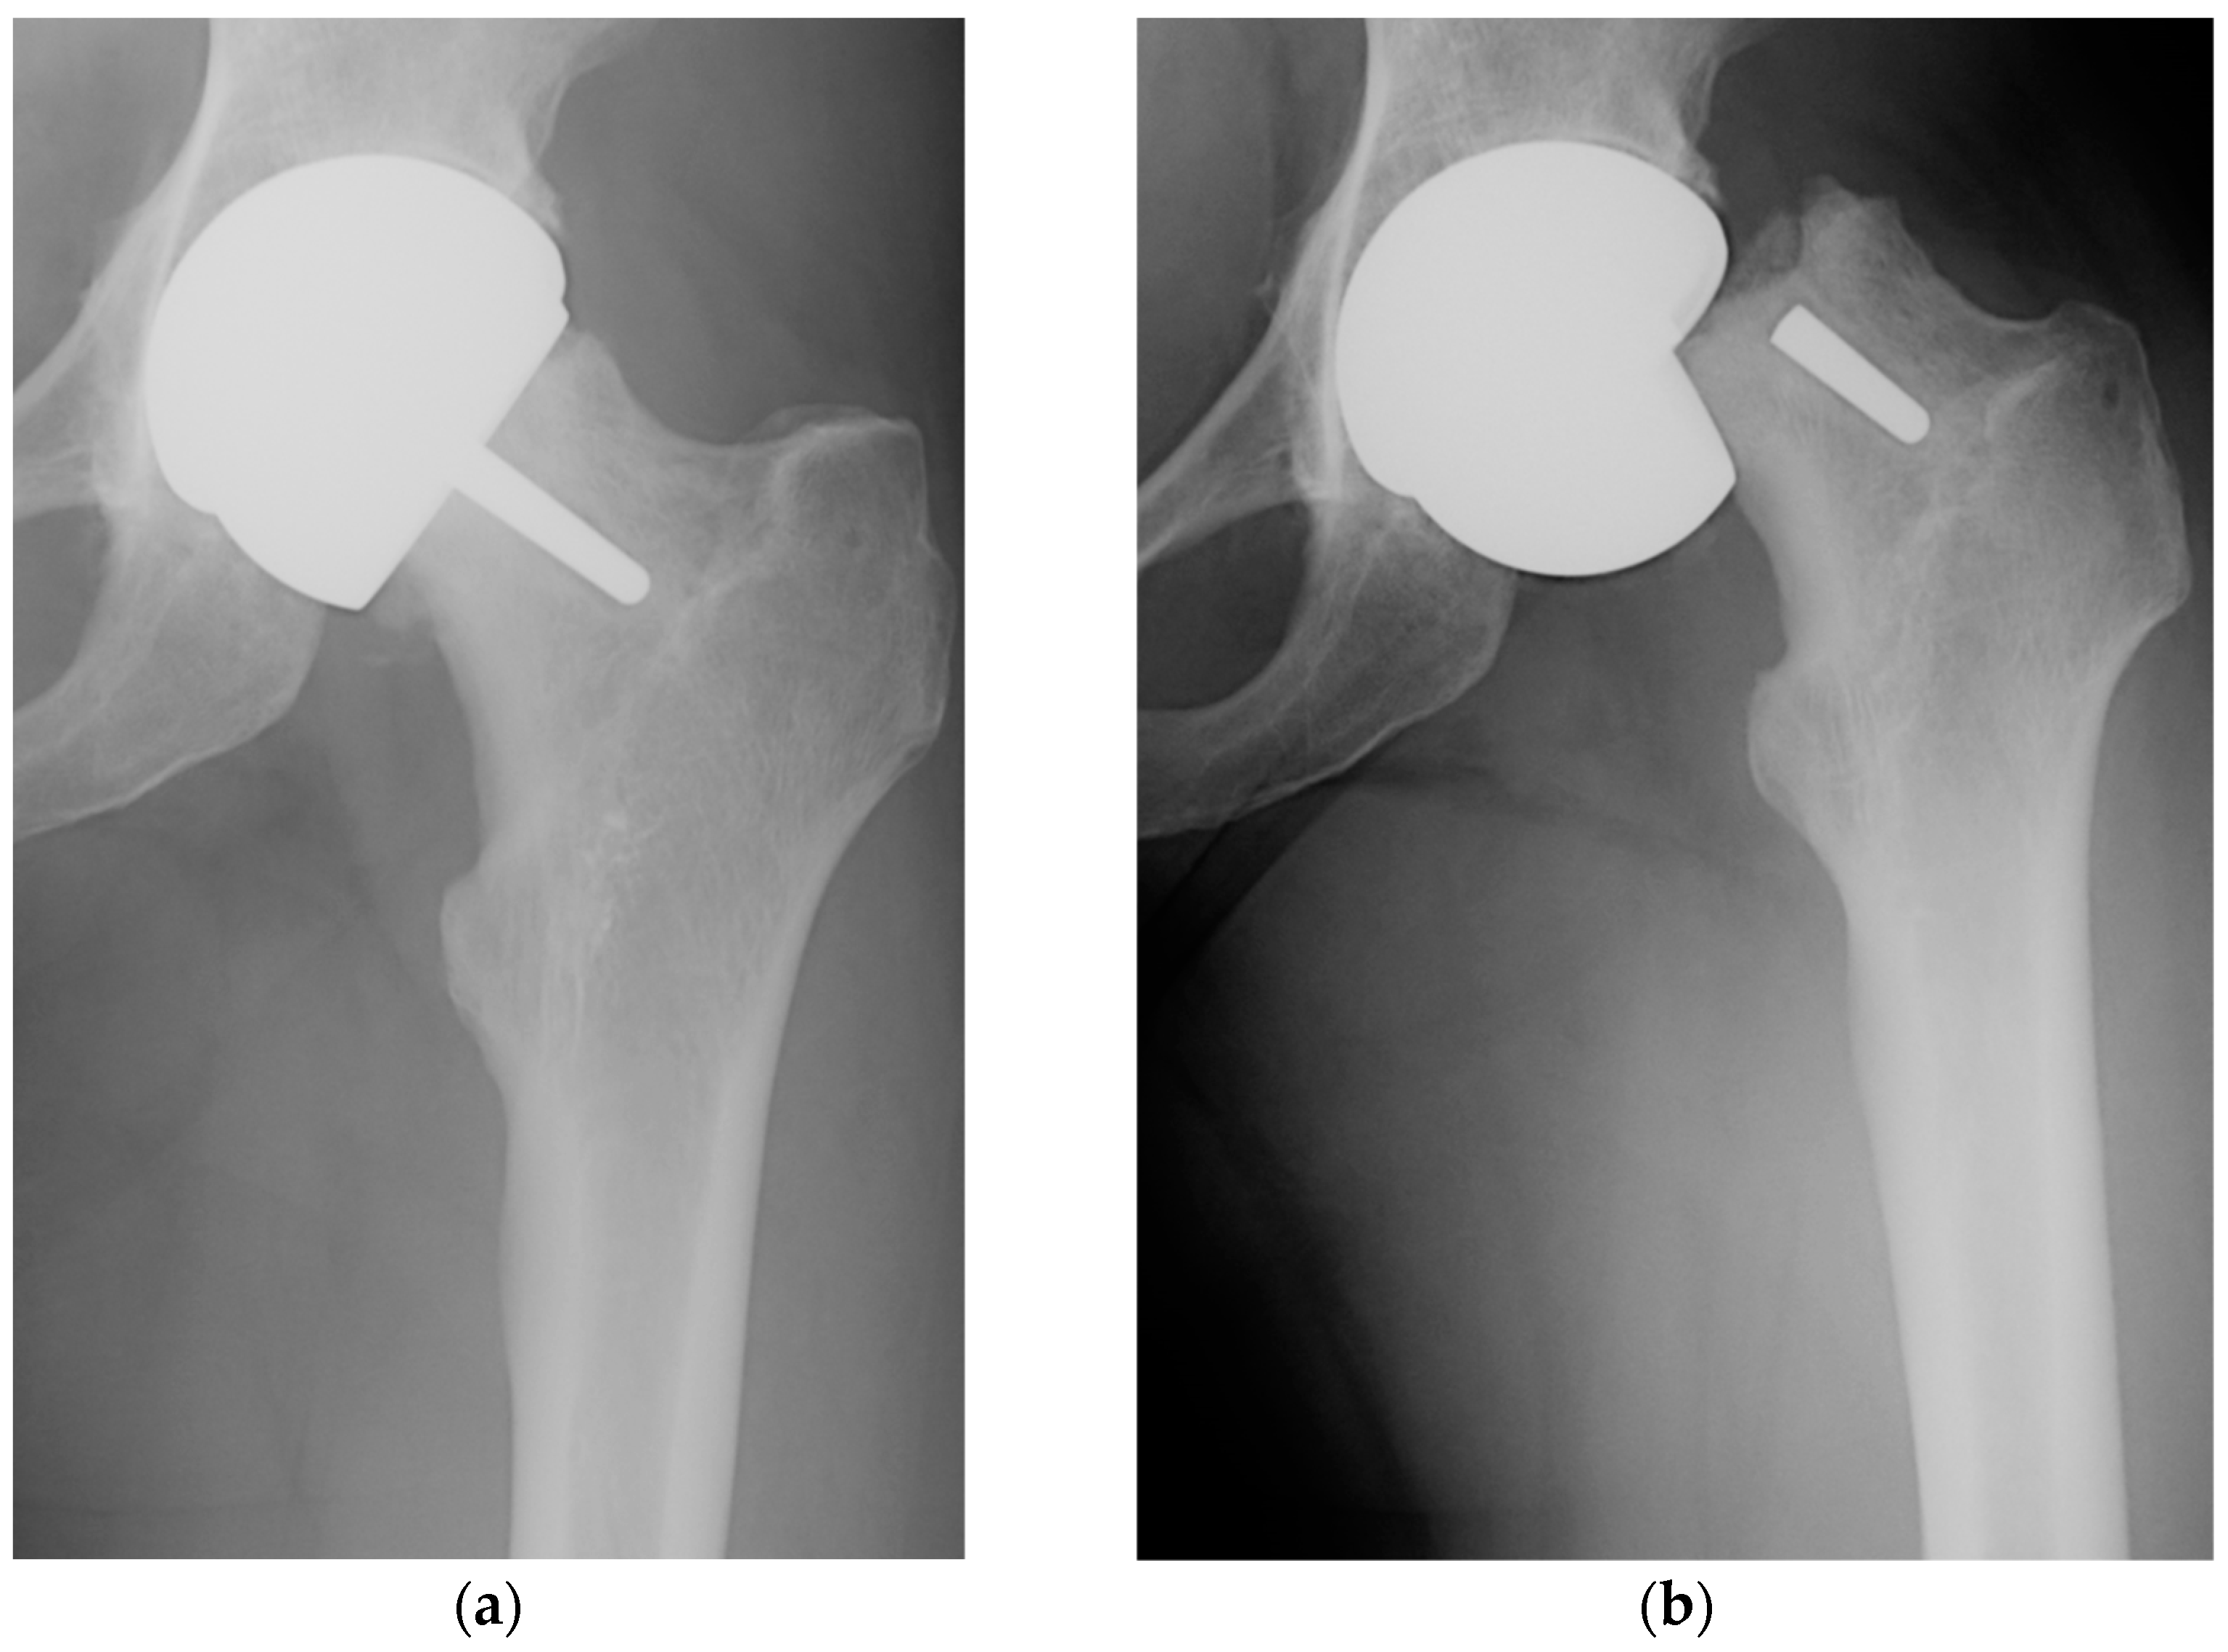

In Figure 1, we present, from our own experience, the roentgenogram of a patient (female, 52 y.o.) with a perceived limp requiring a cane for ambulation, showing the loosening and fracture at the femoral neck that occurred after one month.

Anteroposterior radiographs demonstrating the Birmingham Hip Resurfacing system in situ (a) with femoral component loosening and (b) femoral neck fracture after one month.